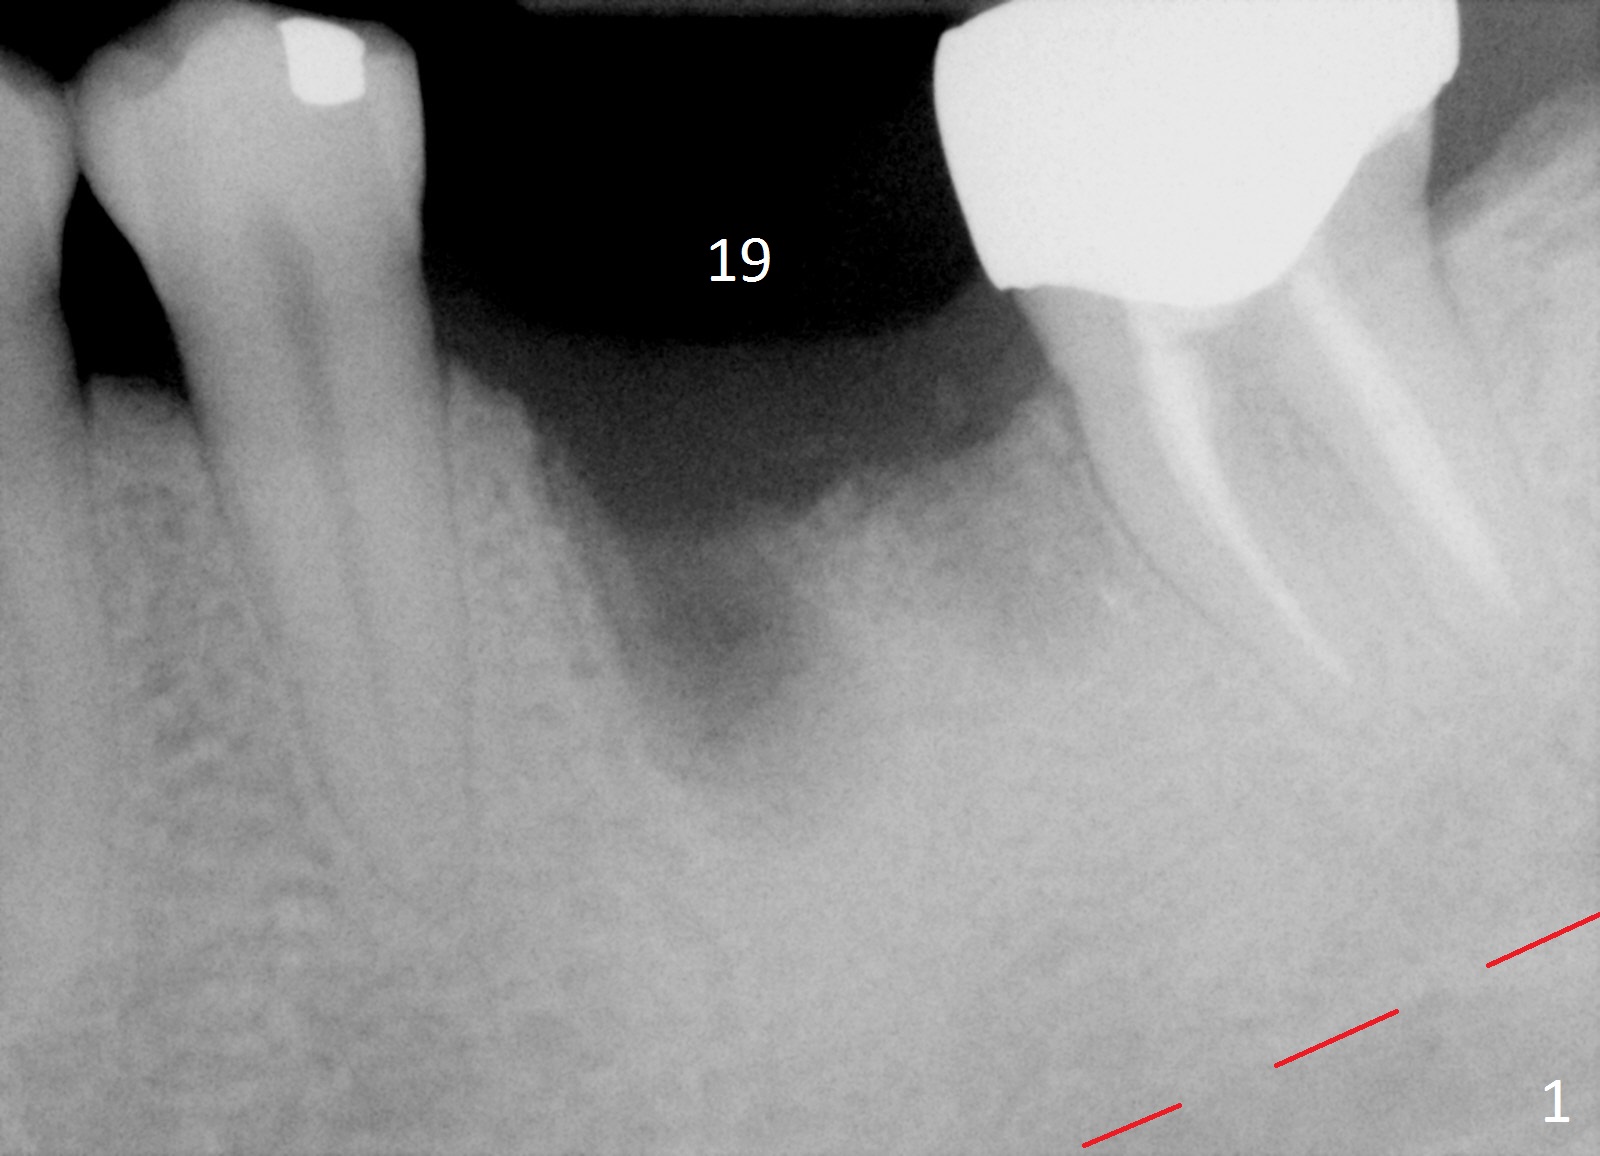

Etiology of Periimplantitis A 42-year-old woman presented to clinic 11 years ago with history of extraction of the tooth #19 two months earlier (Fig.1). Two months later, a 5x8 mm Bicon implant was placed (Fig.2). Integrated Abutment Crown was delivered 2 years later (Fig.3) with persistent radiolucency in the mesial socket. The tooth #18 was extracted with socket preservation 7 years ago. Recently she returned with chief complaint of chewing pain in the lower left for a while. The buccal gingiva of #19 is erythematous, edematous and tender (Fig.4). There are healing abutment at #29 and implant crown at #30. Periimplantitis at #19 is most likely due to buccodistal placement. When it is removed (Clindamycin), a smaller IBS or SM implant will be placed immediately and mesiolingually (Fig.3). For better wound protection with periodontal dressing or provisional, an implant will be placed at #18 at the same appointment. Draw blood for PRF if the vein is large enough. Surgical stents have been in cold sterilant. Return to Lower Molar Immediate Implant, Prevent Molar Periimplantitis (Protocols, Table), Course 1 2 Fig.1 Remedy Xin Wei, DDS, PhD, MS 1st edition 06/16/2017, last revision 06/26/2020 |